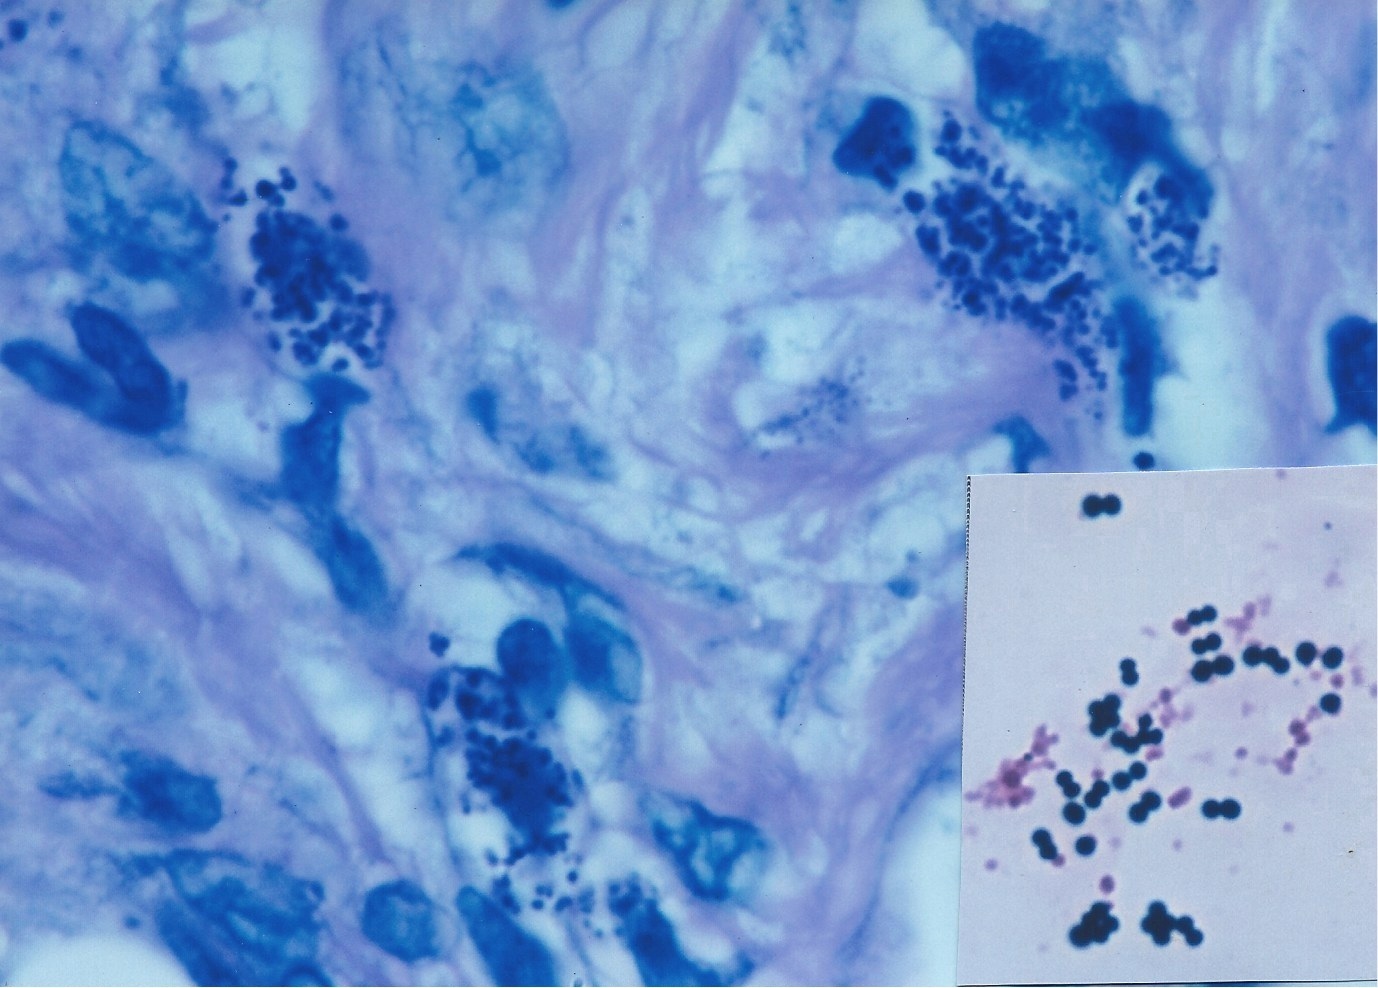

Figure 3 shows the cancer germ appearing as intra- and extracellular coccoid forms in an acid-fast stained tissue section of AIDS-related Kaposi’s sarcoma of the skin.

Figure 3. AIDS-related Kaposi’s sarcoma of the skin showing extracellular coccoid forms in the dermis. Fite (acid-fast) stain, x1000.

in the dermis. Intensified Kinyoun’s (acid-fast) stain, x1000. .Inset shows appearance of Streptococcus viridans cultured from the tumor.

Acid-fast “spicules” (of unknown significance) appear to emanate from the tiny cocci. Ziehl-Neelsen (acid-fast) stain, x1000

Figure 9. AIDS-related Kaposi’s sarcoma of the skin showing intra- and extracellular coccoid forms. Giemsa stain, x1000.

Inset shows various sized and variably stained cocci of Staphylococcus epidermidis. Gram stain, x100